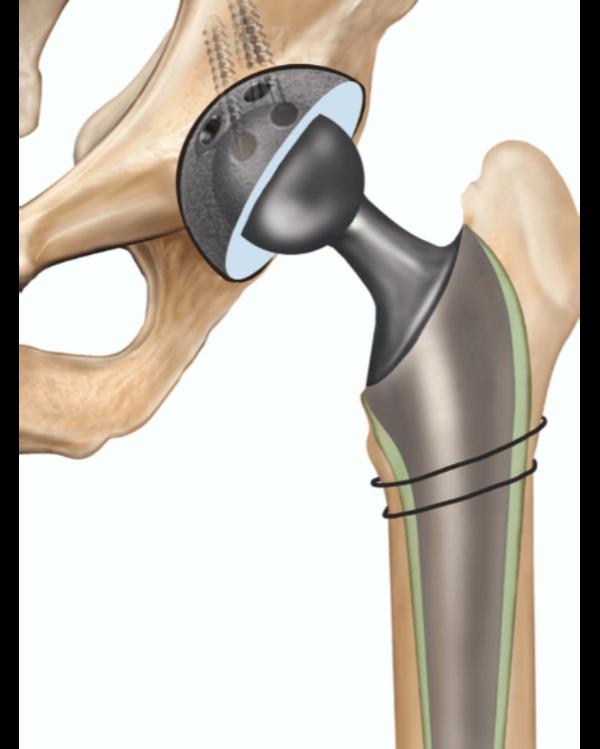

If joint pain is slowing you down, finding the right surgeon makes all the difference. At Phoenix Orthopedic Superspecialty Hospital in Nagpur, we offer expert care from some of the best joint replacement surgeons in the region. Whether you're dealing with arthritis, fractures, or degenerative conditions, our orthopedic team is here to guide you through every step of the recovery process.

Using the latest techniques and personalized approaches, our specialists perform safe, precise surgeries with minimal downtime. We ensure that each patient is well-informed and supported throughout their treatment journey.